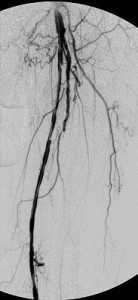

It was , therefore, helpful to the patient that I eliminate as much of the upstream disease as was feasible and dilate the critical stenosis of the left tibioperoneal trunk. Thus, balloon angioplasty was applied to the common femoral obstruction and the tibioperoneal trunk stenosis and a stent-graft was used to exclude from the circulation all the superficial femoral arterial disease. The bottom panel of images shows the immediate outcome of these interventions. The ulcer eventually healed.